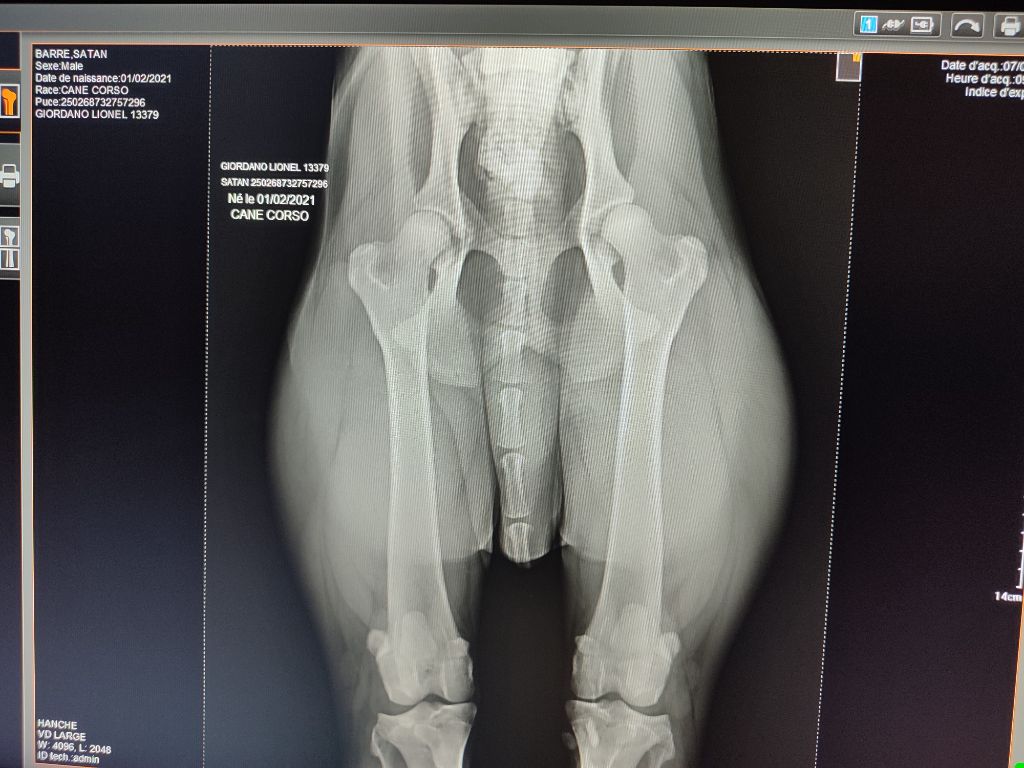

Radiographier hanches B et coudes 0

Radiographier hanches B et coudes 0